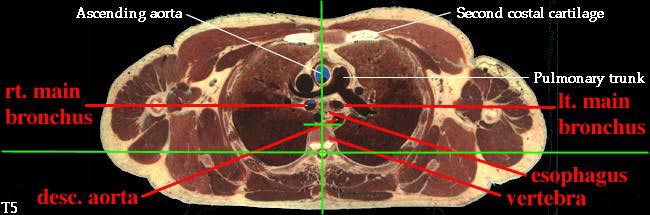

3. Describe the organization of the thoracic sympathetic trunk, in addition to its visceral and splanchnic branches. (W&B 413-416, N158, N160, N165, N209, N240, N254, TG4-45, TG4-46, TG8-03, TG8-14)This set of cross-sections might help (no guarantee!):

- Esophagus: enters the mediastinum a little to the right of the median plane, posterior to the trachea. It passes to the middle of the body, then to the left and anteriorly as it travels down to the stomach. (See "Extra Explanation" below.)

- Descending aorta (thoracic portion): the continuation of the arch of the aorta, supplying oxygenated blood to thorax (except the heart), abdomen, pelvic region, and lower extremities. It begins on the left side, but moves to the midline (to lie on vertebrae) as it descends. The branches of the thoracic descending aorta include: